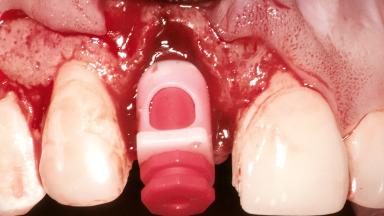

Replacement of a Maxillary Right Central Incisor Using an Early Loading Protocol

A healthy 26-year-old woman was referred for evaluation and treatment of her failing maxillary right central incisor (tooth 11). She reportedly traumatized the tooth at about age 9 and subsequently had repeated conventional and surgical endodontic procedures and fixed restorations. Despite these procedures, she had recurrent fistulas in the apical mucosa and a mid-facial pocket of 7 mm with suppuration. All other sites on the tooth probed 3 mm without inflammation. She presented with a medium biotype with triangularlyshaped teeth and a moderately high smile line, showing all of her papillas and a few millimeters of marginal gingiva in a full smile.Ceramic veneers were present on teeth 12, 21, and 22, and they were known to be somewhat bulky, eventually requiring replacement. She had a strong desire to avoid additional tooth preparation and would not consider a fixed dental prosthesis to replace tooth 11.

Bone Augmentation Horizontal|Simultaneous

Augmentation Materials Autogenous chips|Membrane

Soft Tissue Grafting Simultaneous

Placement Protocol Early or late implant placement

Bone Volume Deficient horizontally, allowing simultaneous augumentation